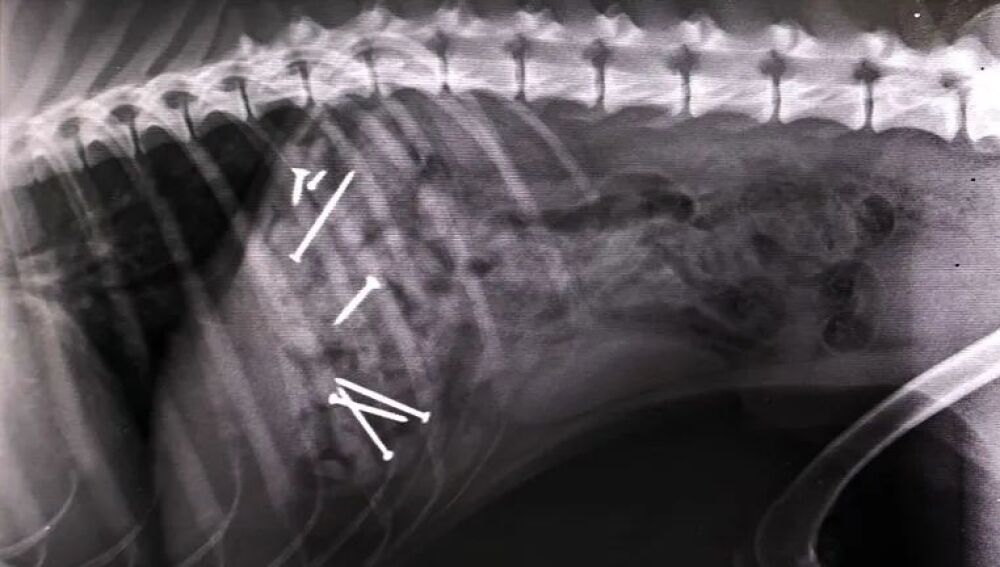

Perro al que intervinieron hace dos años por comer salchichas con clavos en VigoAntena 3 Noticias

En la primera de las ubicaciones se han encontrado salchichas con clavos en su interior. Las esconden entre las hojas y el olor atrae a los perros. Cuando el animal ingiere la comida, es básico llevarlo a un veterinario para que pueda operar al can y evitar, así, la muerte. Pero no es el único cebo que se ha encontrado en los últimos días. En el Arenal la trampa va más allá.